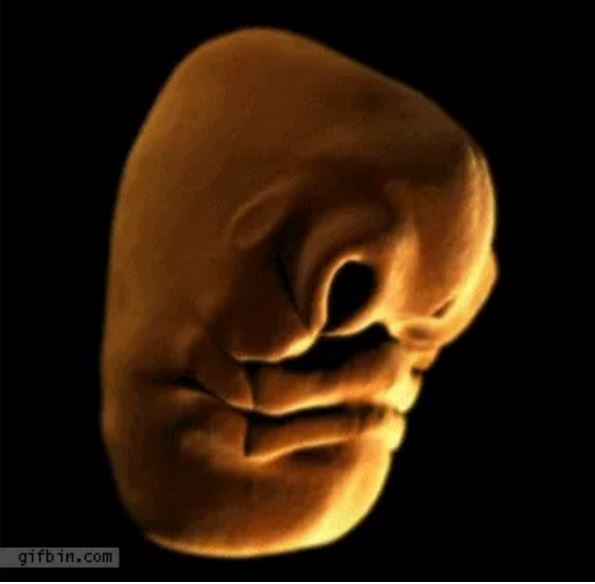

Dị tật này xảy ra trong quá trình hình thành gương mặt của chúng ta. Dành cho những ai chưa biết thì mặt người không phải sinh ra đã có đâu. Trong những tháng đầu tiên của thai kỳ, khuôn mặt sẽ phát triển theo từng phần riêng biệt và tách rời, sau đó mới "ghép" lại như trò xếp hình vậy.

Dị tật này xảy ra trong quá trình hình thành gương mặt của chúng ta.